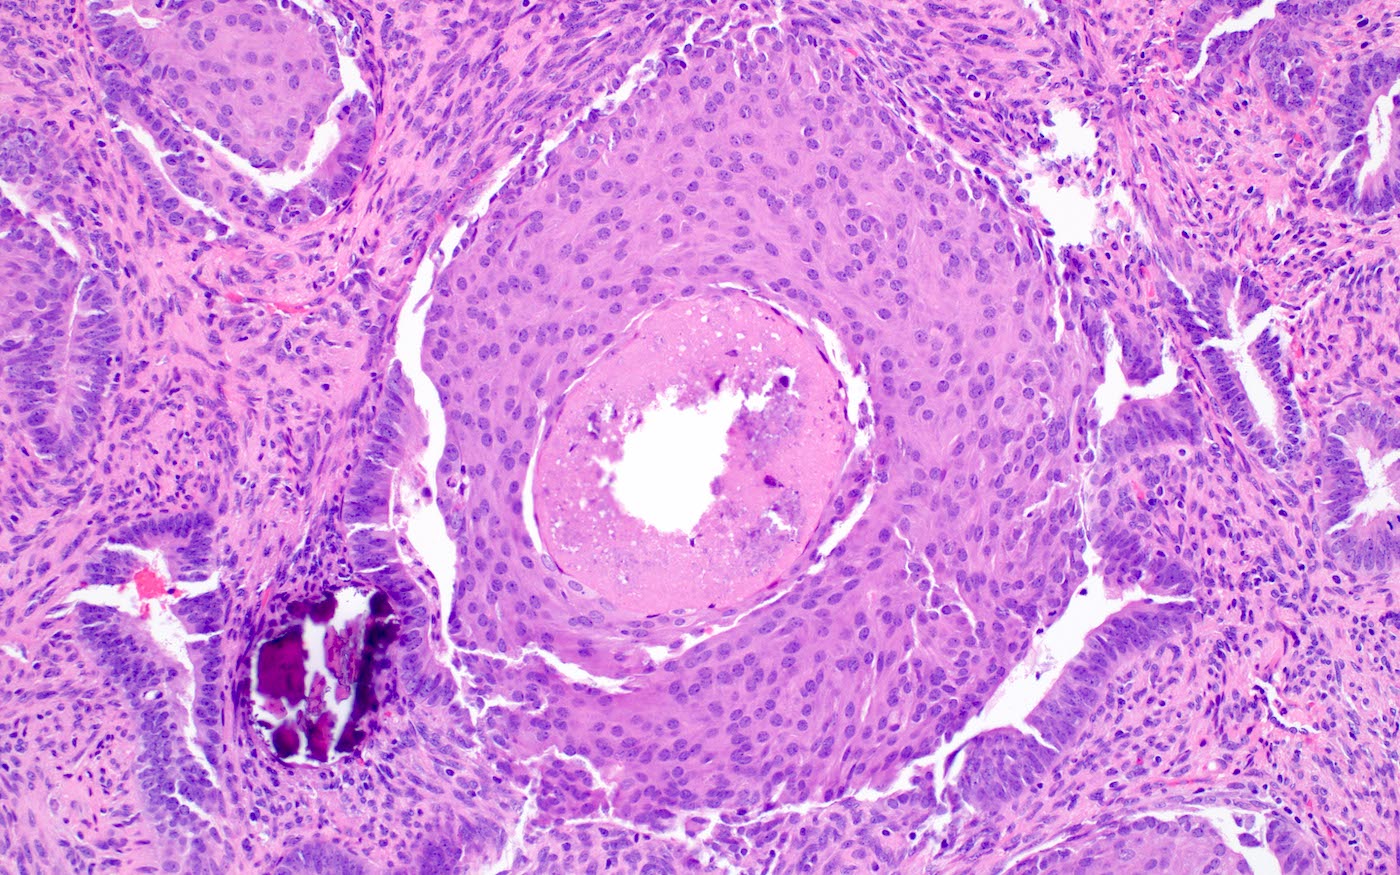

Microscopic (histologic) description

- Biphasic tumor:

- Endometrioid glands, usually with complex architecture and sometimes with cytologic atypia

- Glandular component often shows lobulated architecture

- Benign fibromyomatous stroma, rarely with myxoid change

- Squamous morular metaplasia is frequently seen and may show central necrosis

- Well circumscribed or slightly irregular margin

- Reference: Am J Surg Pathol 2015;39:1148

Microscopic (histologic) images